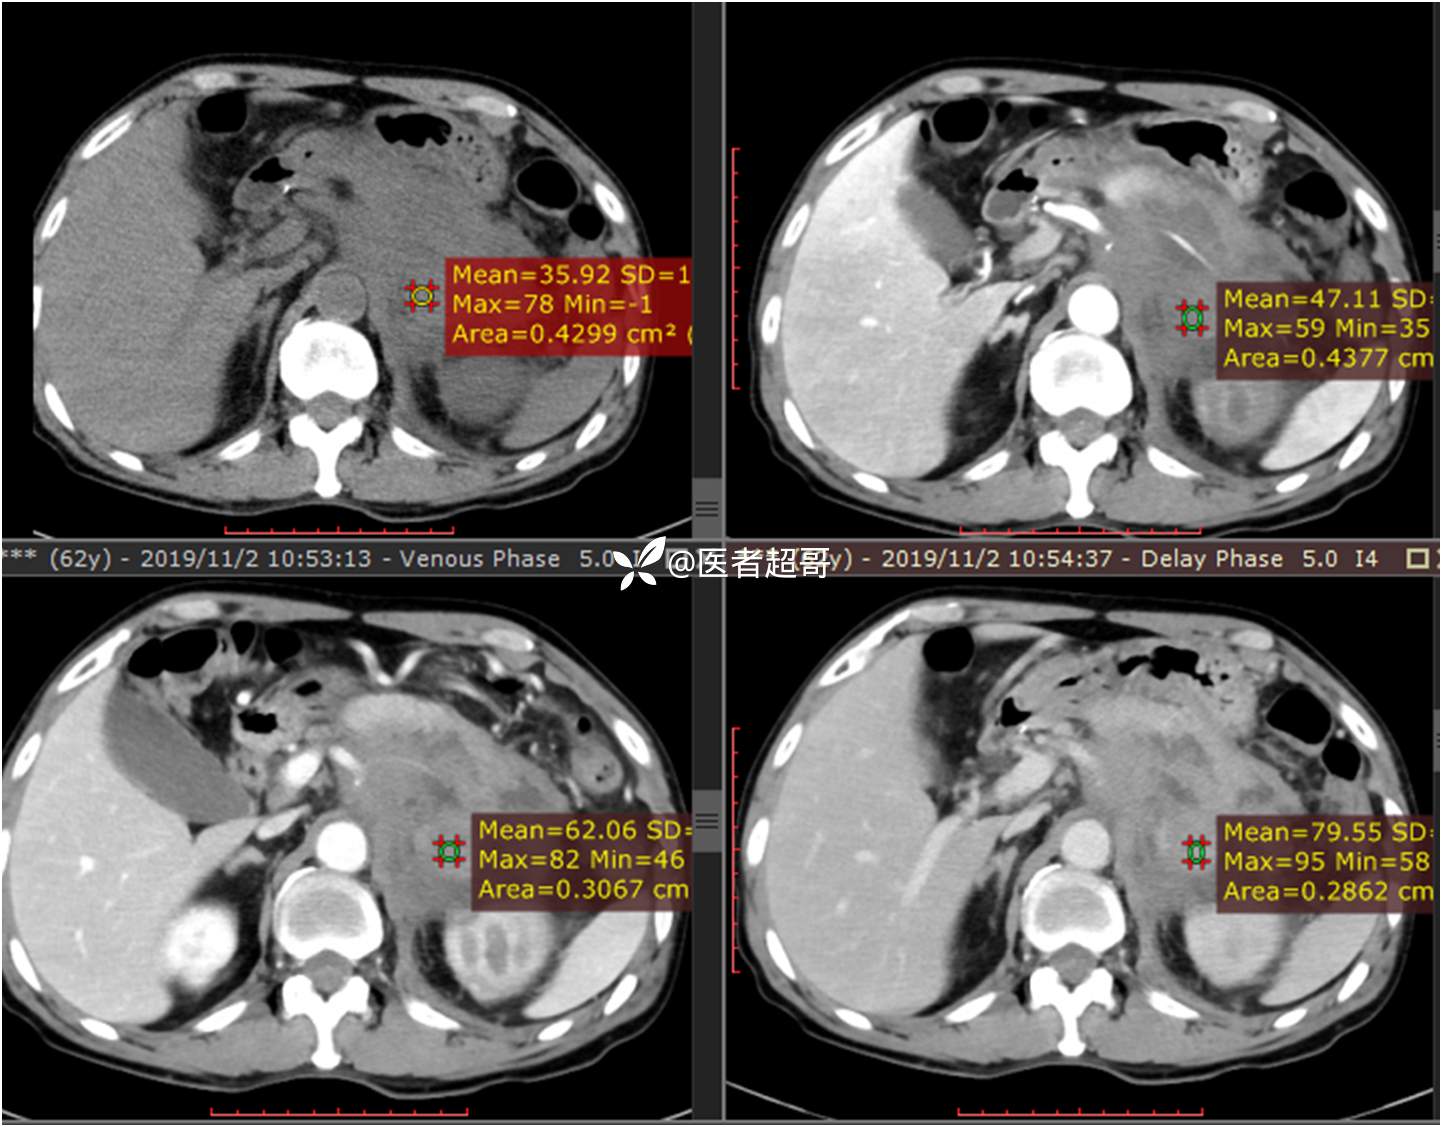

现病史:患者于1月前无明显原因及诱因出现左上腹部疼痛,为间断性疼痛,无恶心、呕吐,无寒战、高热,无腹胀、腹泻等伴随症状,在外未行特殊处理,患者于1周前自觉疼痛加重,为求诊治患者曾就诊于市东城医院,行全腹部强化CT提示:左肾上腺区肿块,符合恶性肿瘤侵犯左肾、胰腺及腹膜后大血管CT表现,行保守治疗,症状缓解,今患者为求进一步诊治,来我院就诊,行腹膜后占位穿刺活检病理提示:(腹膜后占位穿刺)小细胞背景内见细胞浆红染的神经节样细胞,建议到病理科加做免疫组化进一步明确诊断,遂以“腹膜后肿物”收入院,患者自发病以来,神志清,精神可,饮食、睡眠差,大小便正常,体重未见明显改变。